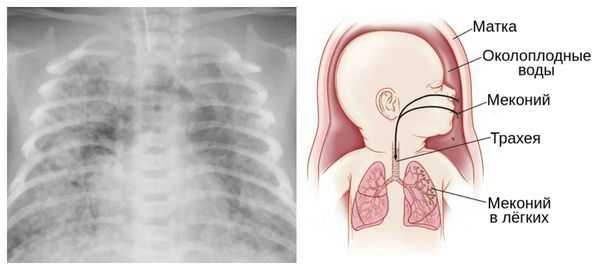

Преждевременные роды, которые происходят в 22-27 недель, составляет 5 % от их общего количества. В первую очередь эти роды обусловлены истмико-цервикальной недостаточностью, инфицированием плодных оболочек их преждевременным разрывом. В этой ситуации легкие плода не достигают еще необходимой зрелости, что не позволяет в достаточной степени обеспечит дыхательную функцию новорожденного. Добиться ускорения созревания легких с помощью лекарственных средств, не всегда возможно. Вследствие этого исход родов для новорожденного в подобной ситуации наиболее неблагоприятный.

Из-за снижения кровотока в почках плода выделение мочи значительно уменьшается, развивается маловодие. Также изменяется характер околоплодных вод: они теряют прозрачность, становятся мутными, приобретают желтоватый или зеленоватый оттенок из-за примеси мекония — первых фекалий ребёнка.

За счёт изменения состава околоплодных вод нарушается выработка сурфактанта — вещества, которое не даёт альвеолам слипаться во время выдоха. Это вызывает патологию лёгочной ткани и нарушение дыхания после рождения. Также снижается защитная функция лёгких: в водах увеличивается число бактерий, что повышает риск инфицирования лёгочной ткани [1] [8] [11] .

Для плода большую опасность представляет асфиксия (острая гипоксия) и отслойка плаценты. Нехватка кислорода внутри утробы стимулирует плод выполнить несвоевременные дыхательных движения. Они приводят к заглатыванию вод и возможному воспалению лёгочной ткани — пневмониту. Если в водах есть примесь мекония (первородного кала), то велика вероятность мекониальной аспирации — проникновения содержимого кишечника новорождённого в его лёгкие.